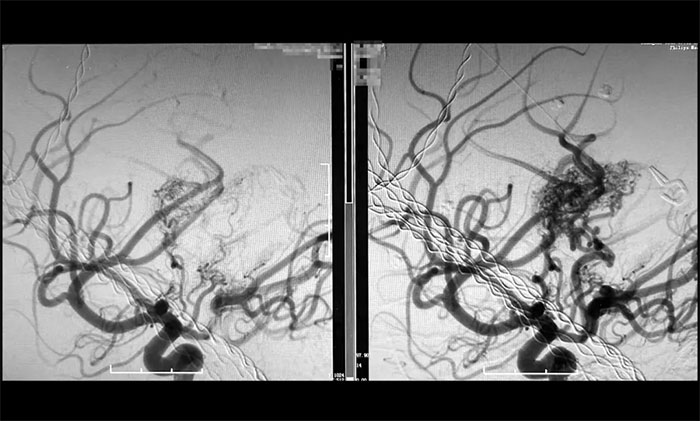

近期,卢云鹤博士团队成功完成一例高难度巨大脑动静脉畸形栓塞术。该病例为儿童脑深部核心功能区高危复发型AVM,血流动力学复杂(伴盗血和静脉球),且已多次出血,患儿危在旦夕。如果不治疗,必然再次出血,下一次可能就是灾难性的。再次手术治疗,就如同走钢丝,面临着术中即刻的大出血和脑梗死两大致命/致残风险。最终,卢云鹤博士团队迎难而上,在多支穿支动脉供血并合并假性动脉瘤的极端条件下,借助术中功能监测(电生理+mini-wada试验)辅助下,成功实施超选择性介入栓塞,最终实现畸形团完全栓塞,且未造成神经功能损伤。

▲ 巨大脑动静脉畸形(右)被顺利栓塞(左)